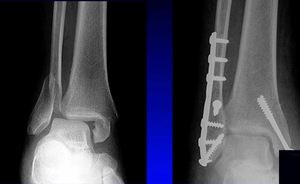

We don’t necessarily operate on all ankle fractures. The following x-ray demonstrates a stable ankle fracture (Figure 1).

This patient can start immediate, protected, weight bearing in a boot or air cast. If you’re not practicing that, you should! I still see elderly patients with a small “crack” like this, that are kept non-weight bearing for two months. Don’t do that! These are stable injuries. They can start immediate, protected, weight bearing in a boot, and can wean out of the boot as tolerated.

The more interesting question is, “what about unstable ankle fractures, and what do you do after surgical fixation, in terms of when do you allow them to start weight bearing and start ankle range of motion?”